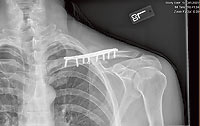

If you are like me when I had extensive oral surgery, broke my clavicle, and had orthopedic surgery, you don’t have months, weeks, or even days to recover. You’ve got plans. Whether it’s going on a trip, getting back to work, getting back on your bike, simply getting out of pain, or whatever, you don’t have time to lay in bed or sit around watching Netflix while your body does what it was designed to do.

The reason you have never heard about these tools is because they don’t involve drugs. Unlike my broken clavicle, many injuries don’t require surgery—just some cutting-edge tools we use in the office on a daily basis. Although a speedy recovery can require an investment, you don’t have to be a pro athlete to afford it. At Prestige Wellness Institute, we utilize a comprehensive approach to giving the body everything it needs to recover in a hurry.

Using these tools, I had extensive oral surgery, attended a national medical conference in another state (with a broken clavicle), then had orthopedic surgery, all in the span of six days--and did not miss a single day of work. I was back on my mountain bike—EZ’ing into it at Bar M—21 days (instead of 10 weeks) after surgery.